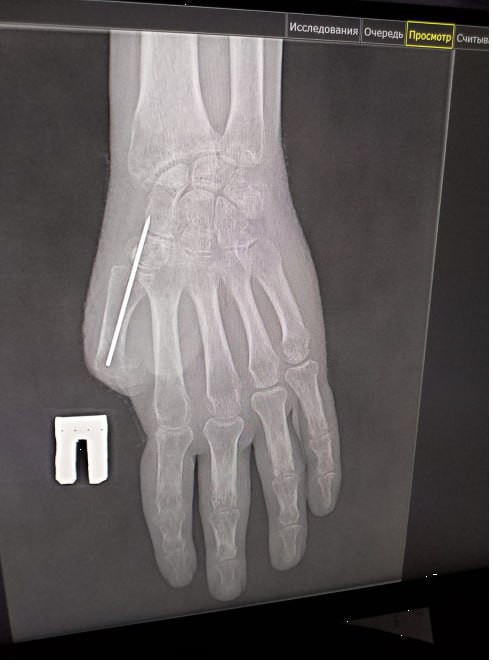

Прокопьевские врачи восстанавливают участнику СВО большой палец руки, который он потерял в результате взрыва.

Первую операцию провели в начале этого года. Заведующий микрохирургическим отделением Прокопьевского ортопедо-хирургического центра Андрей Сигарев убрал грубые рубцы и виртуозно сформировал основу для будущего большого пальца.

В ходе следующей операции специалисты сформировали первый луч кисти и выполнили пластику «китайским лоскутом» – пересадили на кисть лоскут ткани с собственными сосудами. Такая методика гарантирует полноценное кровоснабжение и надежное приживление.

В ближайшее время проведут коррекцию прижившегося лоскута и углубление межпальцевого промежутка, чтобы придать кисти еще больше функциональности и естественный вид.